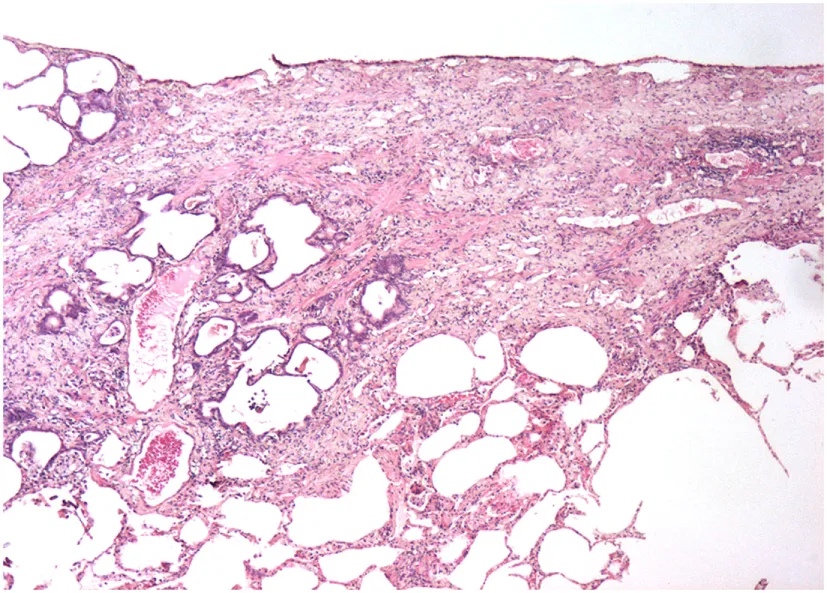

A study on Westies (109) found that the majority of dogs with IPF showed multifocal areas of accentuated subpleural and peribronchiolar fibrosis with occasional “honeycombing” and profound alveolar epithelial changes, reminiscent of human UIP and not commonly seen in NSIP. Interstitial fibroblastic foci, characteristic of UIP, were not seen in WHWTs with IPF. Progressive fibrosis, with intra-alveolar organizing fibrosis alongside interstitial mature collagen deposition, was present within the more severely affected areas of lung in WHWTs with IPF. Severe pulmonary lesions were seen more commonly in the caudal than in the cranial lung lobes.

The ubiquitous gammaherpesvirus equine herpesvirus 5 (EHV 5) has been detected in lung tissue from horses that develop progressive pulmonary fibrosis and is now considered to be the likely cause of this disease in these animals (111). The pathology of this disease is distinct from human IPF, demonstrating multiple nodules and is therefore termed equine multinodular pulmonary fibrosis (111). Although the pathology is not the same as IPF, there are striking overlapping features including weight loss and gradual exercise intolerance, accompanied by characteristic radiologic features (111). Temporal heterogeneity or fibroblast foci, hallmarks of human disease, are not present in the disease in horses, though these characteristics have been described in feline pulmonary fibrosis (111, 112). Similar to EBV in humans, which has been associated with IPF, EHV 5 is a ubiquitous subclinical gammaherpesviral infection in horses (113). Considered largely non-pathogenic in the natural host, some strains of EHV5 appear to be pathogenic and capable of inducing lung fibrosis (103). While EHV5 was isolated from horses with spontaneous disease, the virus was not isolated from dead inoculated horses that developed lung fibrosis (111). This model raises interesting questions regarding induction of lung fibrosis by EHV 5 during viral latency versus lytic infection.

The authors acknowledge the Lester and Sue Smith Foundation, Coalition for Pulmonary Fibrosis, and the Pulmonary Fibrosis Foundation for their support. The authors also acknowledge Amy Miele, BVM&S MRCVS (University of Edinburgh) for her contributions in providing veterinary histopathology images used in the construction of Table 1. AT is a recipient of a Marie Curie/Sklodowska ERS/RESPIRE 2 fellowship (8860-2015). All authors have no financial affiliations or conflicts of interest to disclose.